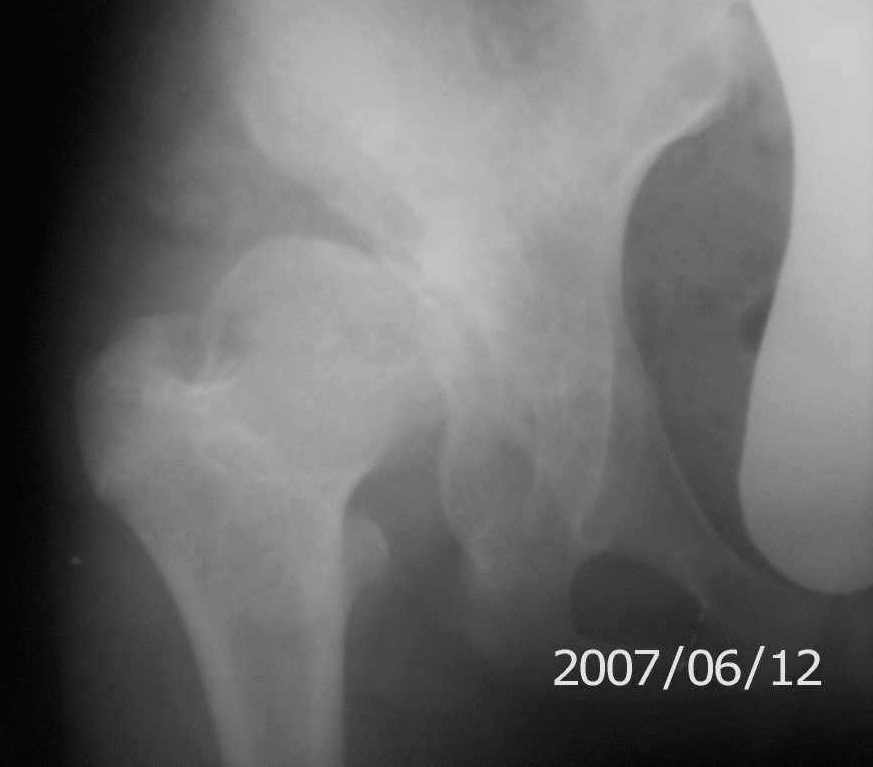

On x-rays coxa magna, shallow true + pseudoacetabulum.Options: salvage

( Shelf /Chiari) or triple osteotomy.Trudno otvetit bez at least basic x-rays.

Ацетабулюм крайне недоразвит. Есть высокий подвывих, можно даже сказать вывих с формированием ложного ацетабулюм. Для головки нет покрытия совсем и расположена она высоко.

На мой взгляд - SHORTENING OSTEOTOMY , VARUS если надо (на основании снимка во внутренней ротации), репозиция головки, CHIARI OSTEOTOMY или SHELF OPERATON Спасибо за интересный случай.